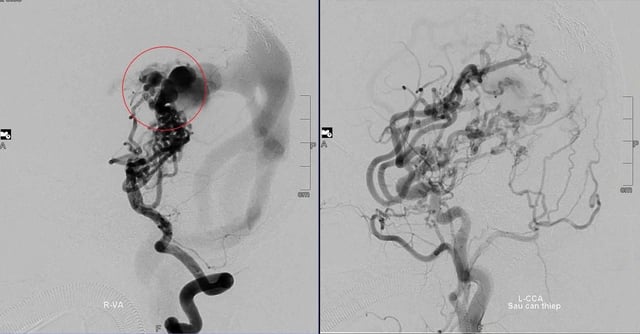

Baby D:s cerebrala vaskulära missbildning före och efter flera interventioner.

När lilla D. bara var ett år gammal utförde Dr. Tran Chi Cuong den första interventionen i Da Nang. "Detta var en enorm utmaning. Missbildningen var för komplicerad, patienten var för ung och interventionsverktygen var begränsade", berättade experten.

Lyckligtvis lyckades det första fallet över förväntan. Läkarna konsulterade och beslutade att ingripa i flera steg för att minska blodflödet och förhindra risken för att missbildningen skulle brista.

"Under de senaste 10 åren har D. genomgått 8 hjärnkärlsoperationer. Från att ha varit förlamad och haft svårigheter med rörelse och språk kunde D. stå och gå stadigt vid 3,5 års ålder. Nu studerar och leker han normalt, precis som andra vänner i samma ålder."